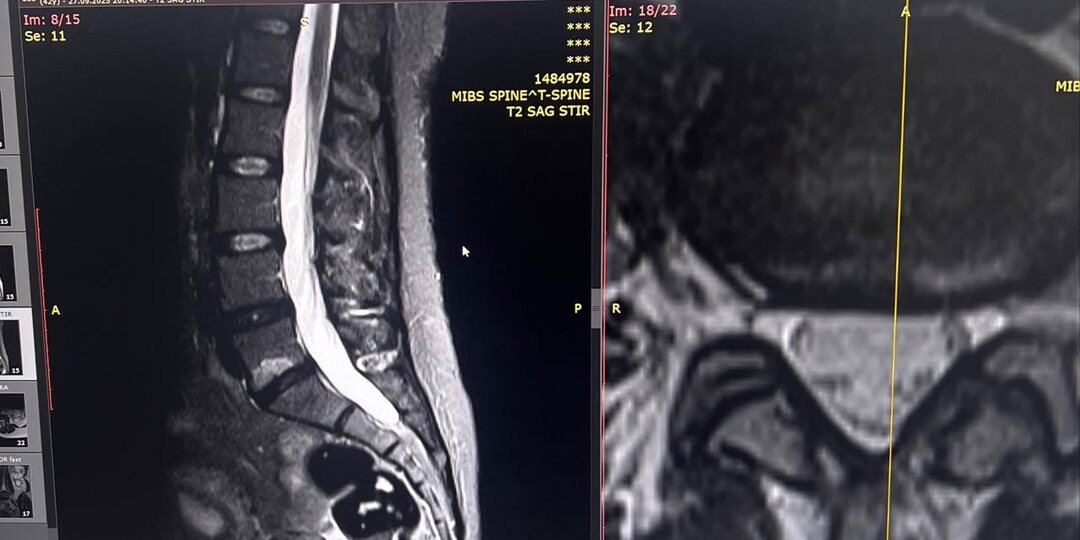

Когда МРТ показывает «воспаление» в позвонках, а врачи пожимают плечами

Представьте: делаете МРТ поясницы, а в заключении написано что-то вроде изменения по типу MODIC . Врач смотрит на снимки, хмурится и говорит: «Ну, есть какие-то изменения в позвонках...» И всё. Никто толком не объясняет, что это значит и почему у вас болит спина уже полгода. Что такое изменения MODIC простыми словами? Думайте о позвонках как о многоэтажном доме. Межпозвоночный диск - это амортизирующая прокладка между этажами. А изменения Modic - это когда в «фундаменте» позвонка (костном мозге) начинается переполох. Modic 1 тип - это как пожар в подвале. Воспаление, отёк, всё горит. На МРТ это выглядит как яркое пятно - сигнал SOS от вашей кости. Modic 2 тип - пожар потушили, но вместо нормальной ткани выросло что-то вроде жирового склада. Кость «сдалась» и заменила активную ткань на пассивную. Modic 3 тип - всё заросло рубцовой тканью, как заброшенное здание бетонными плитами. Почему это происходит Главная причина - диск теряет герметичность. Представьте, что между этажами дома пр